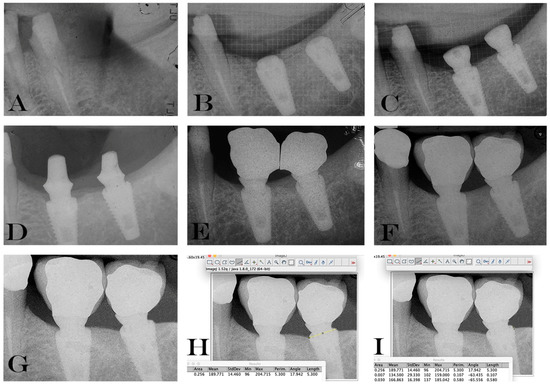

2.5. Data Handling and Radiographic Analysis of Marginal Bone Level Changes.